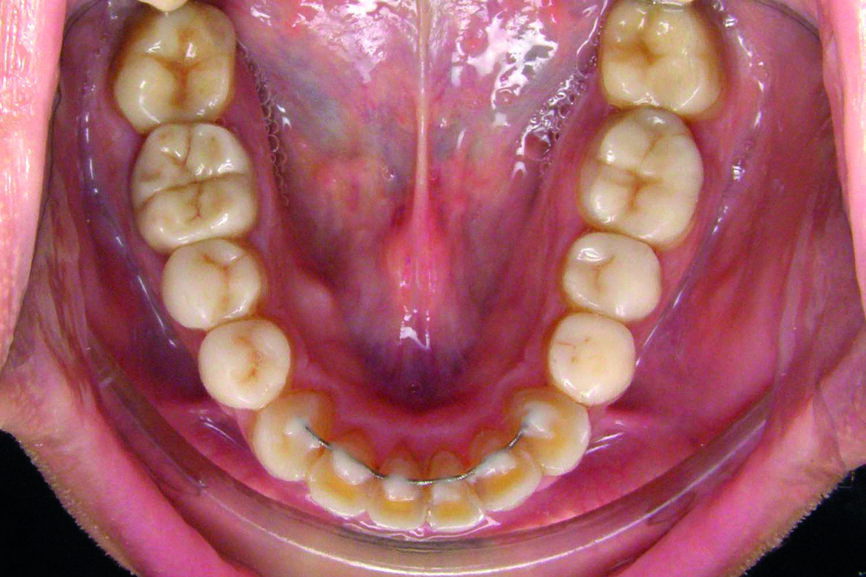

Six mois plus tard, le patient est revu en consultation. Le port de la gouttière (au maxillaire supérieur) a été parfaitement toléré. On entreprend alors les préparations des faces occlusales des molaires et prémolaires mandibulaires, afin de coller des overlays en céramique e.max à la nouvelle hauteur définie. La supraclusion antérieure ayant ainsi été entièrement corrigée et stabilisée de façon prothétique par les overlays collés, une nouvelle gouttière de bruxisme est réajustée aux nouveaux volumes dentaires et sera remise au patient.

Huit mois plus tard, le patient revient pour un contrôle et un détartrage. L’examen de l’ATM est normal. Aucune nouvelle facette d’abrasion sur les facettes prothétiques n’a été constatée. On peut donc aborder la deuxième étape thérapeutique : le traitement esthétique par les aligneurs orthodontiques Cheeez (laboratoire Crown Ceram), afin de corriger les encombrements antérieurs au niveau de la mandibule. À noter que tous les documents étayant le cas ont été pris à ce stade.

D’un point de vue dentaire le patient présente une Classe II division 1, avec une classe II molaire complète et une classe II canine.

- L’arcade inférieure présente un encombrement dans le secteur antérieur associé à une version vestibulaire.

- Stripping de 0.2 mm entre les dents 42/43, 32/33 et 33/34. Les strippings se feront juste avant la pose de l’aligneur trois.

- Mise en place d’une contention collée à la mandibule en fin de traitement.